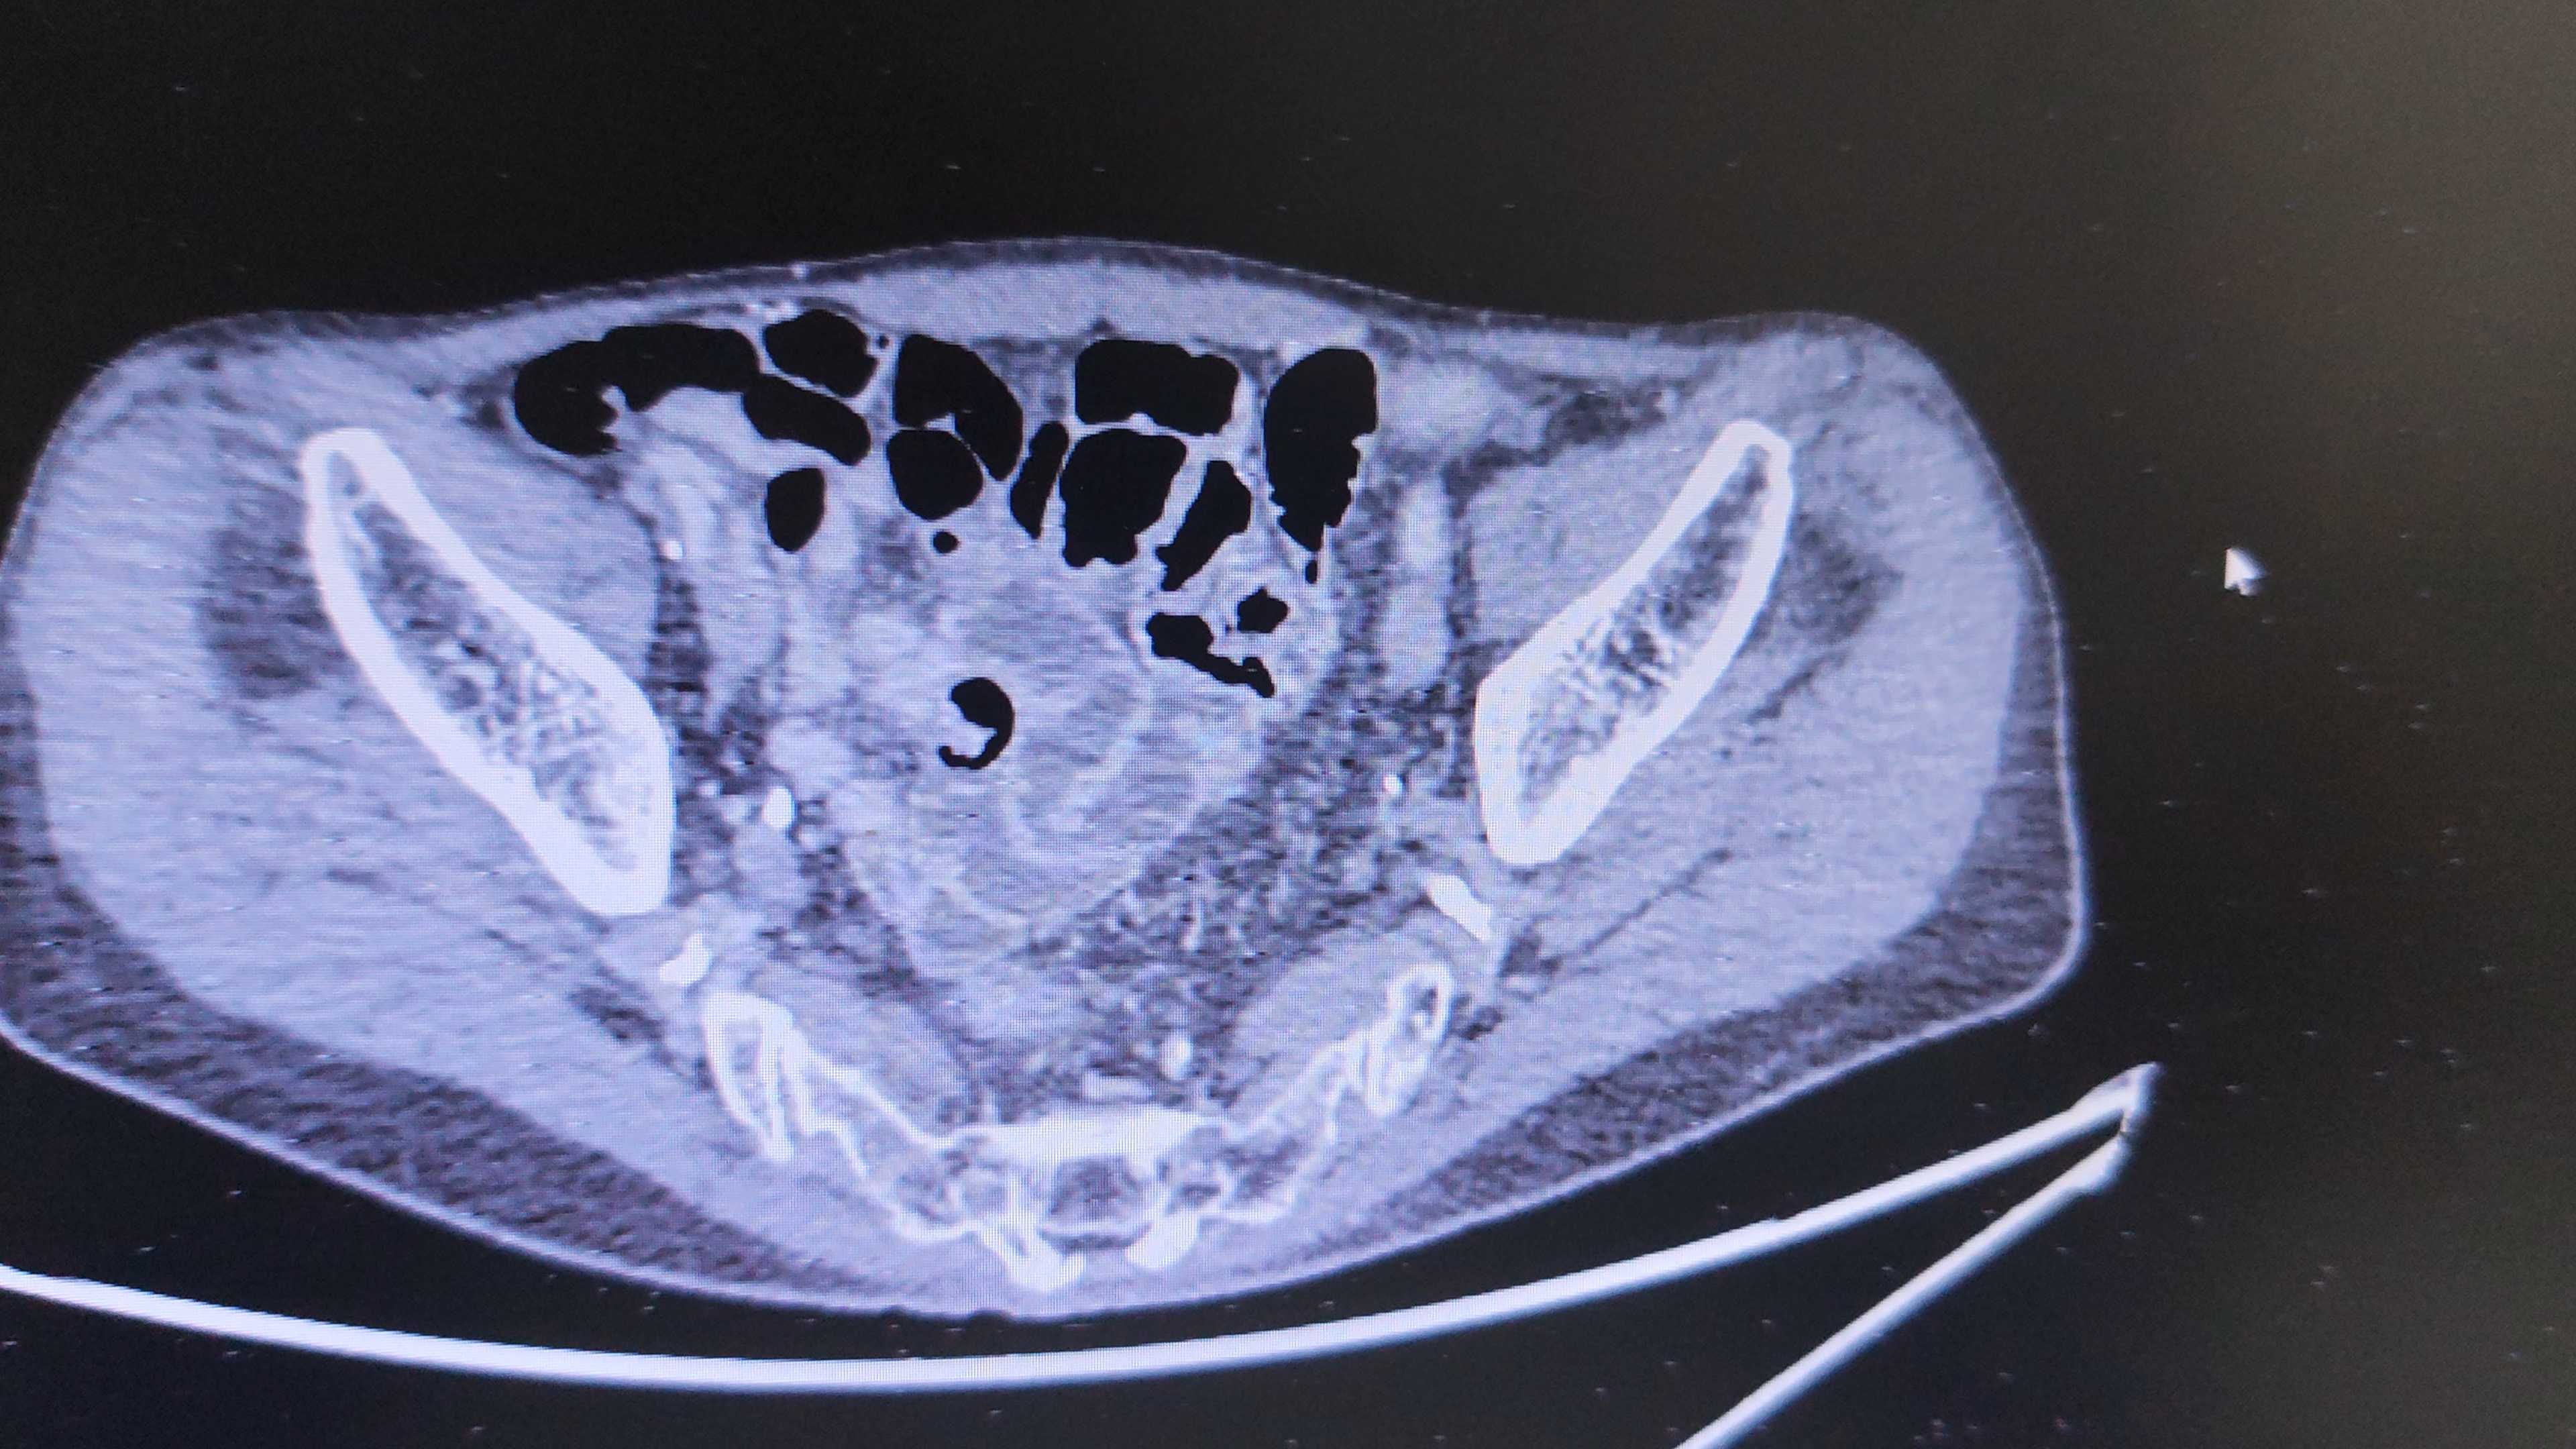

患者男,83岁,间断肉眼血尿2年余,加重1月。

既往史:高血压病,冠心病。

增强CT检查